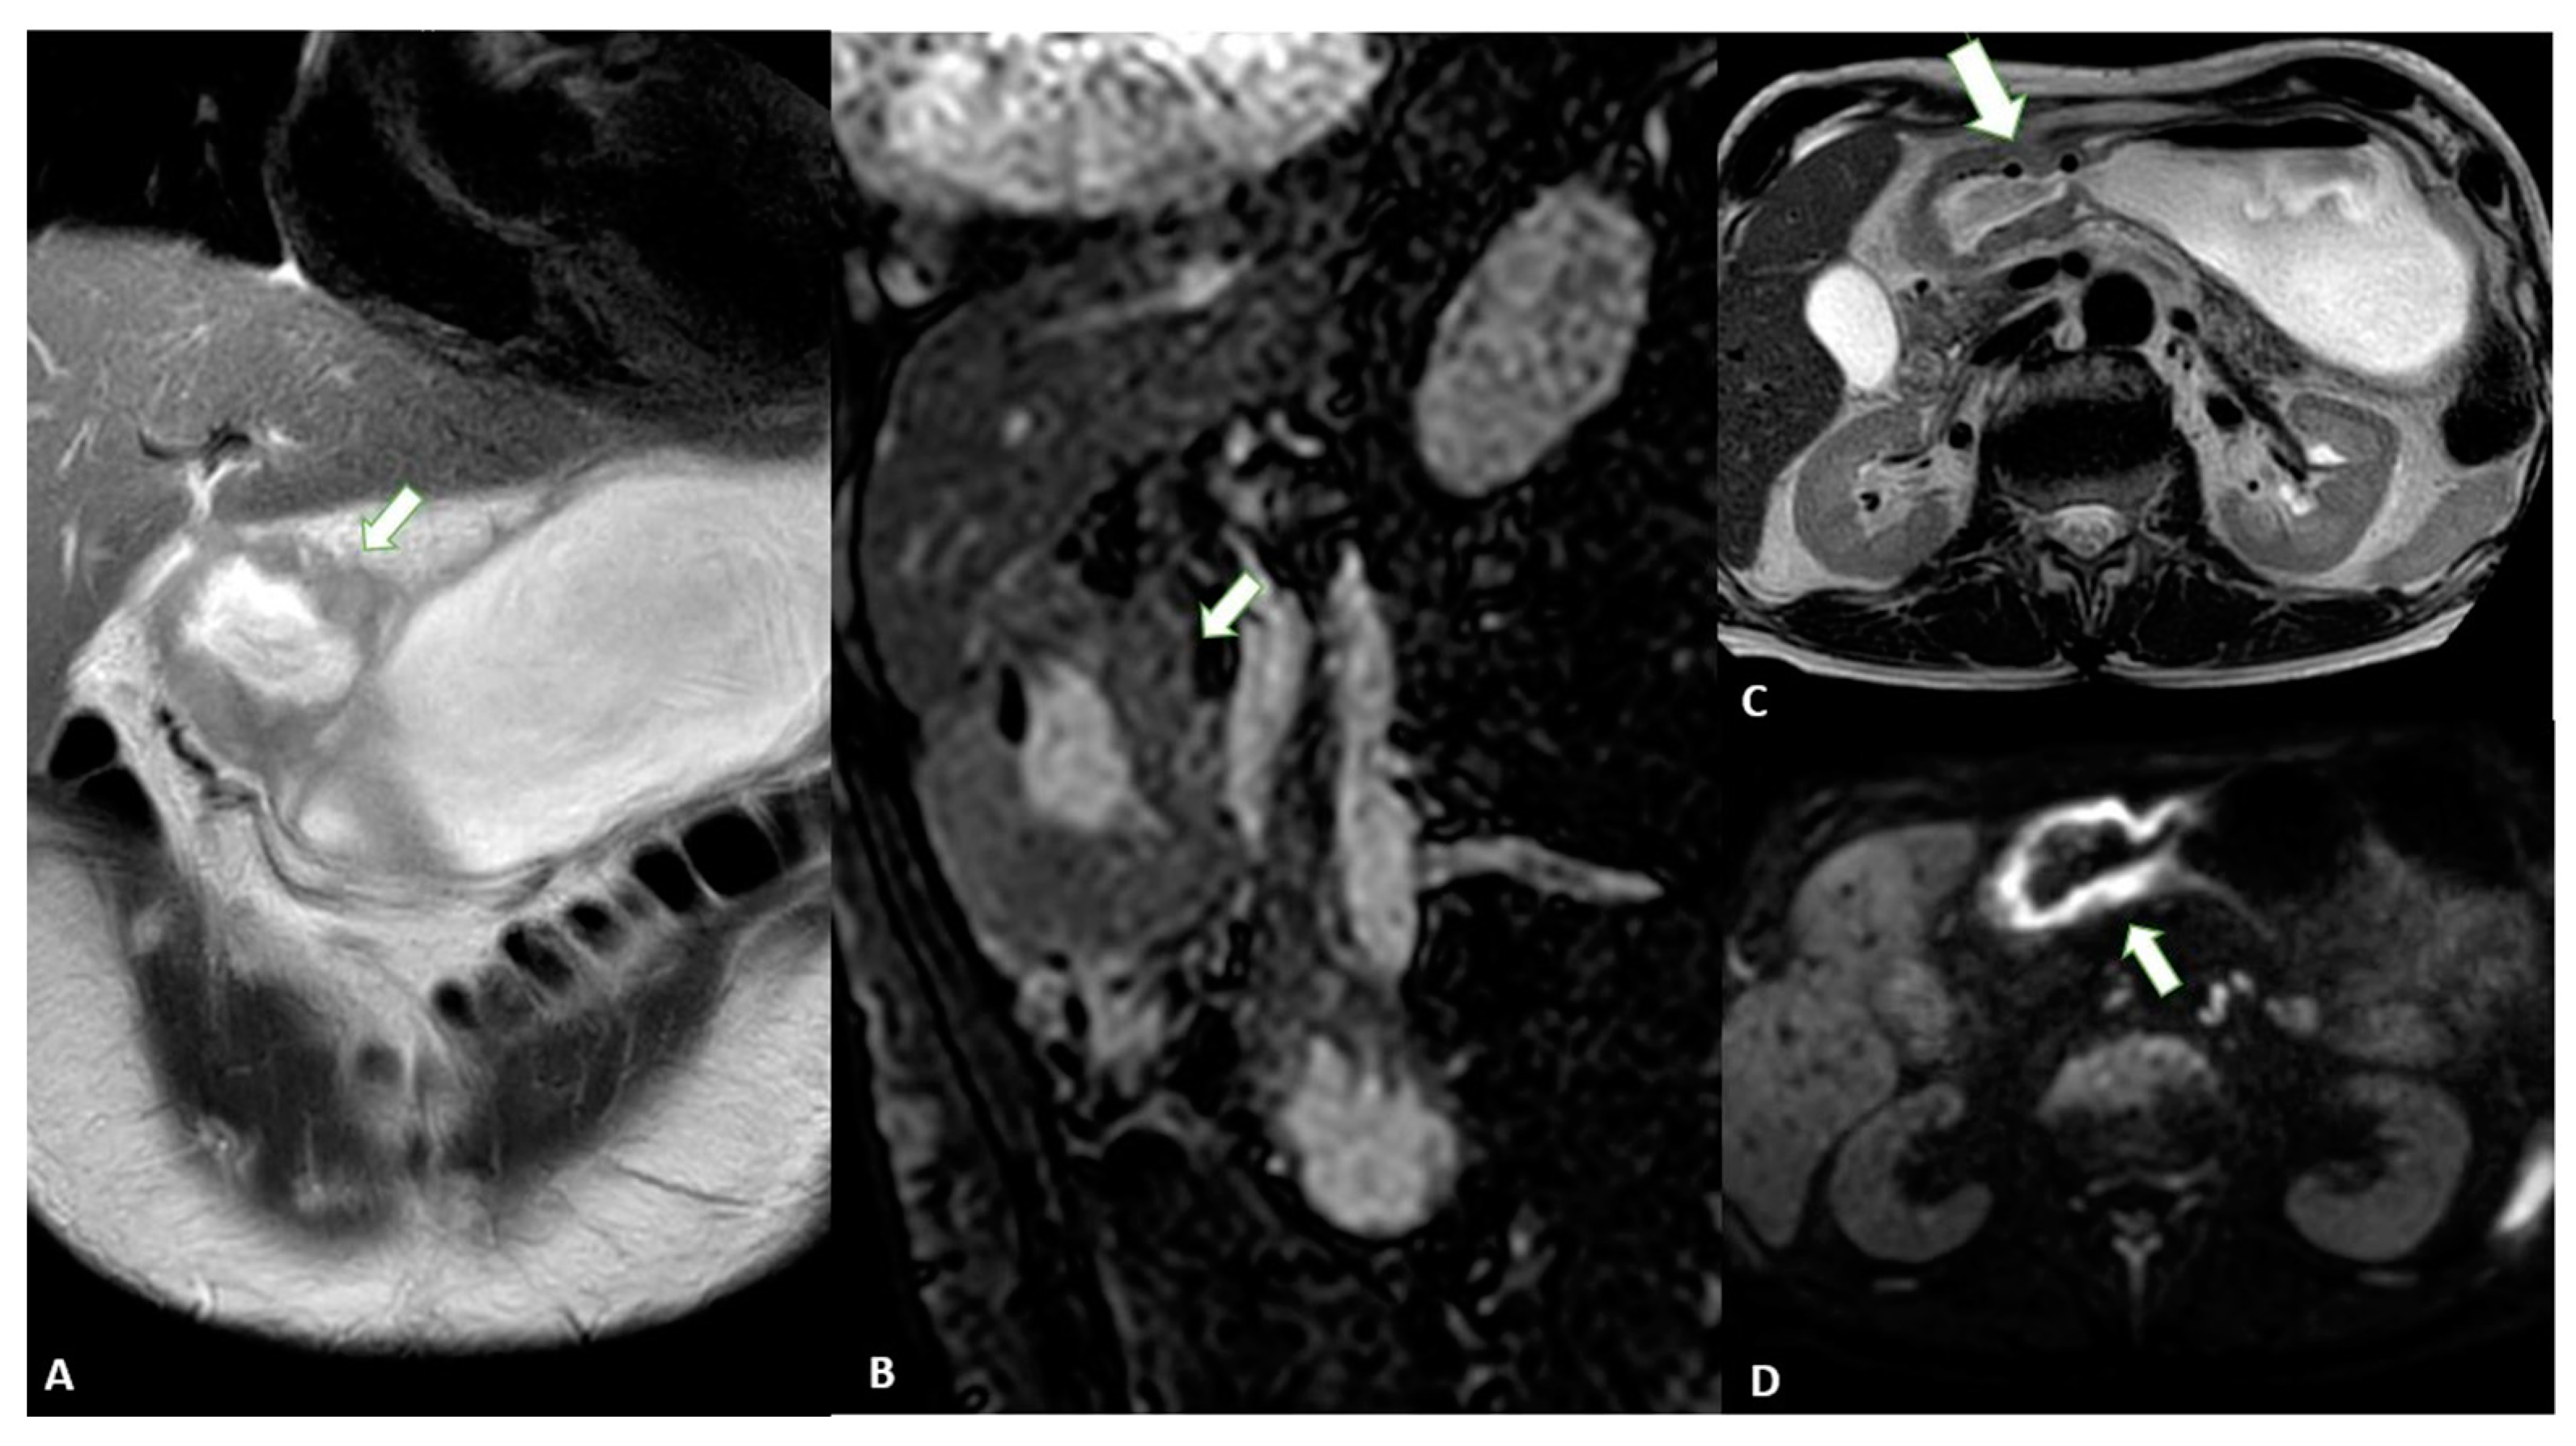

Advances in imaging techniques, such as the introduction of diffusion-weighted imaging (DWI), may provide important data for the definitive diagnosis of various pathologic entities. In this context, DWI can help to distinguish T4 from the lower stages of GC with a high reliability [49]. The authors reported a sensitivity of 92.1%, specificity of 75%, and accuracy of 89.1% for ≤T2 vs. ≥T3 lesions and a sensitivity of 75%, specificity of 88.5%, and accuracy of 82.6% for ≤T3 vs. T4 lesions in 46 patients (Figure 9).

Figure 9.

MRI images of a T3 gastric cancer of the gastric antrum in a 79-year-old male patient. (A) Coronal 2D image and (C) Axial 2D image of the Turbo Spin Echo (TSE) T2 sequence showing a circumferential lesion (arrow) invading the subserosa layer with an intermediate signal intensity; (B) Coronal 2D Balance Fast Field Echo (BFFE) sequence showing a circumferential lesion (arrow) with a low signal intensity; (D) Axial Diffusion Weighted Image (DWI) showing an area of signal restriction (arrow) corresponding to the tumor.

Another study reported that the diagnostic accuracy of DWI in T staging, lymph node staging and distant metastasis is comparable to that of CT, with DWI performing better in the detection of nodal metastasis [50]. In addition, some authors [51] have highlighted the use of DWI in the assessment of the T stage in patients with gastric cancer. By evaluating 51 patients who underwent MRI, the authors demonstrated that DWI can significantly increase the overall detection accuracy for all lesions (88.2% vs. 76.5%, p = 0.031).